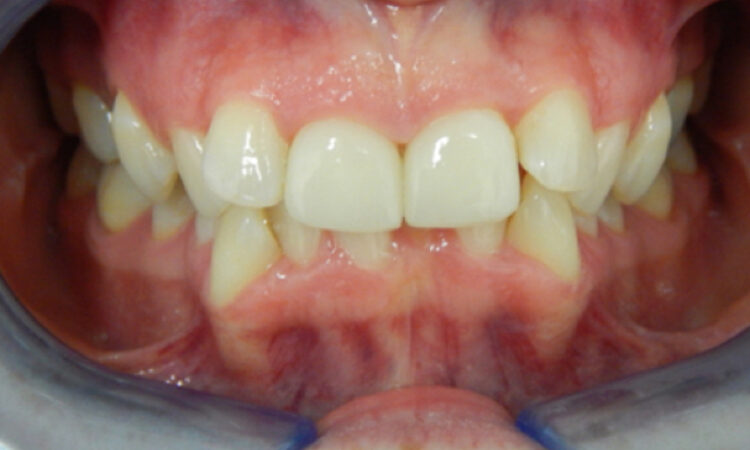

Before - puredental After - puredental

Case 18 - Invisalign®